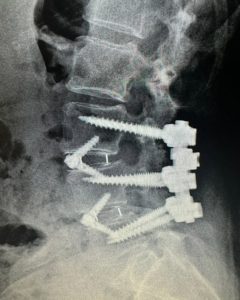

Lin underwent a complex two-level lumbar fusion at Texas Neuro-Spine Surgery. The procedure involved an anterior lumbar interbody fusion (ALIF) at L3-4 and L4-5, followed by laminectomies and pedicle screw instrumentation at the same levels. These surgeries were performed to help address her back issues and improve her mobility.